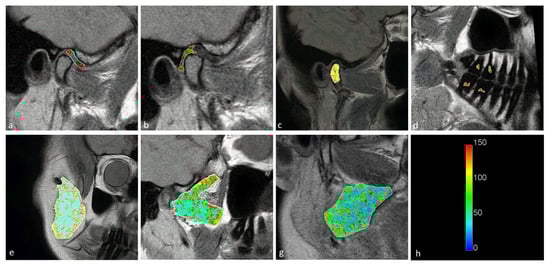

Statistically significant differences were observed between the displaced and nondisplaced disk groups in the retrodiscal tissue short T2 component (p < 0.0001) short fraction (p = 0.0050) and long fraction (p = 0.0049), the medial pterygoid muscle short T2 component (p = 0.0025) as well as the bone marrow long T2 component (p = 0.0030) and short T2 component (p = 0.0116), indicating the relationship between disk displacement and quantitative MRI features of stomatognathic anatomical structures. The pulp short T2 component showed a trend toward statistical significance (0.0125 < p < 0.0500). Sample T2 maps are presented in Figure 2 and Figure 3. Short and long fraction components are presented in Figure 4 and Figure 5, respectively. The Shapiro–Wilk test confirmed normality in all comparisons.

Figure 2. Short T2 maps obtained for the (a) disk; (b) retrodiscal tissue; (c) bone marrow of the condyloid process; (d) pulp; (e) m. masseter; (f) m. pterygoideus lateralis; and (g) m. pterygoideus medialis. (h) Color scale showing the reference T2 times in seconds.